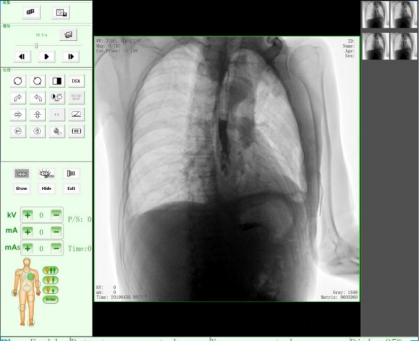

動態DR17*17英寸非晶硅動態平板探測器,透視像素達200萬,可實時顯示大幅面高清拍攝視野。適用于全身各部位攝影,包括常規攝影,如胸片、頸椎、腰椎、腹部、頭顱、四肢等,以及特殊攝影。

適用于全身各部位的透視檢查及輔助治療,如隱匿性肋骨骨折、胸透檢查、骨折復位、小兒腸套疊空氣灌腸等。同時具備多種幀率透視模式,影像更加流暢、準確。